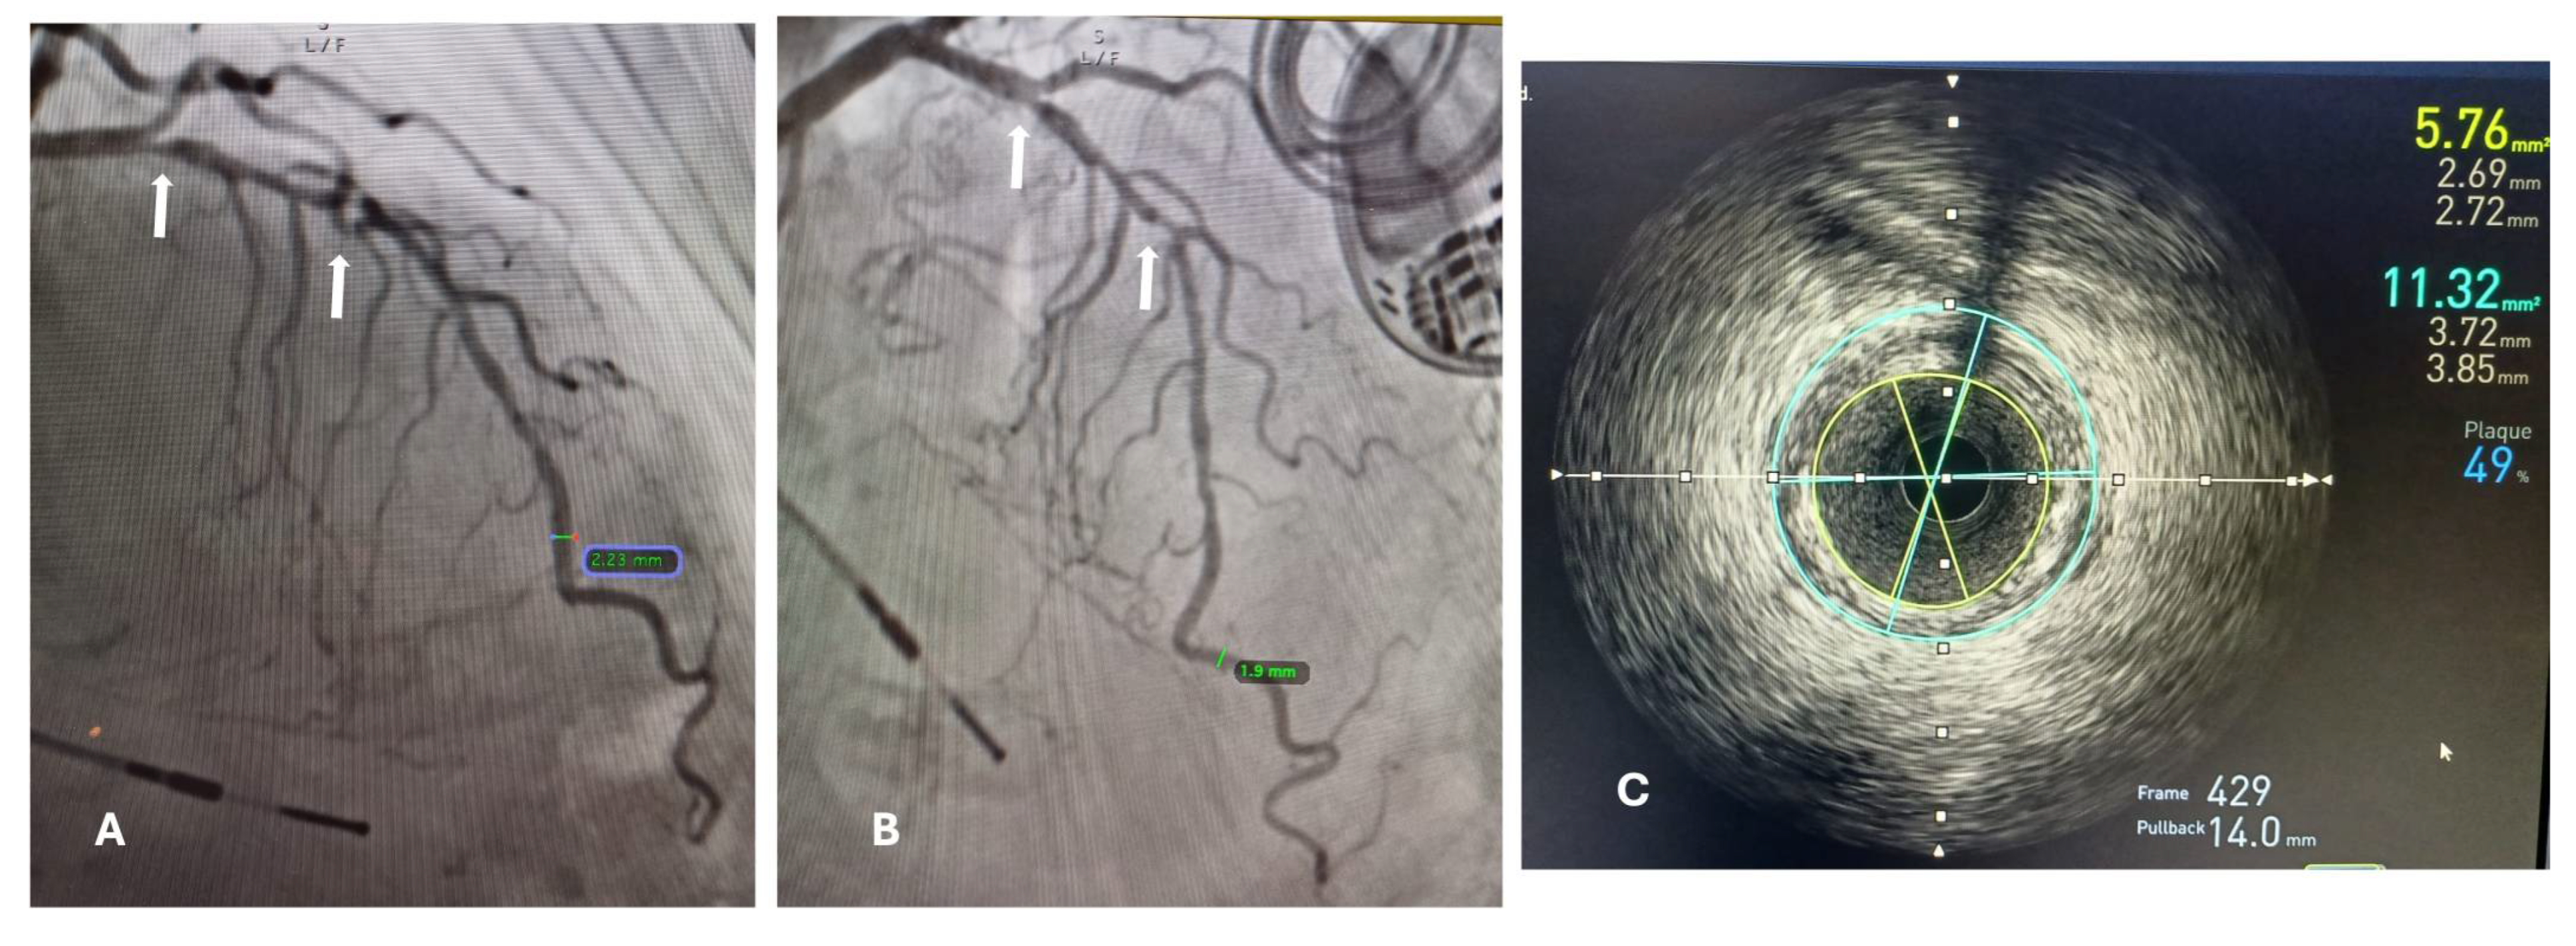

Figure 1. (a) Coronary angiography findings, show a 85% stenosis in the mid-left anterior descending coronary artery (white arrows), the diameter of the affected vessel was measured in the most normal-looking segments distal form the lesion, reported as 2.23 mm. (b) Coronary angiography with a lateral view of the same vessel, where the most distal lesion is better appreciated, the vessel diameter in this view (distal segment) was of 1.9mm. (c) IVUS-guided diameter measurement of the same vessel, the blue circle represents measurement of the reference vessel diameter (RVD) of 3.85-3.72 mm, and the yellow circle represents the remaining luminal area as a result of and obstruction of 49%, due to an atherosclerotic plaque, which is the minimal lumen diameter (MLD) of 2.69-2.72 mm.

The minimal lumen diameter of affected small blood vessels was measured with PCA and IVUs (intravascular ultrasound), and we searched for a correlation among these measurements (Figure 1).